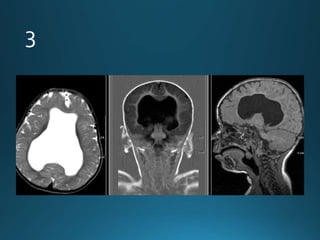

Giant cerebral aneurysms are ones that measure >25 mm in

greatest dimension.

Clinical presentation

Patients can present with symptoms and signs of mass effect

or subarachnoid haemorrhage 1,2.

Pathology

Most commonly represent saccular cerebral aneurysms but

may also be fusiform or serpentine in morphology .They are

thought to develop via two pathways :

• internal elastic lamina de novo defect

• enlargement from a smaller aneurysm

MRI

On MRI also the patent and thrombosed aneurysm display different imaging

features:

T1

most of the patent aneurysm appears as flow void, or they may show

heterogeneous signal intensity

in thrombosed aneurysm appearance depends on the age of clot within the

lumen

T2

typically hypointense

laminated thrombus may show a hyperintense rim